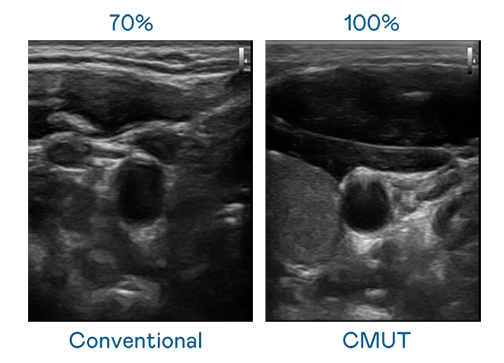

CMUT 技術是一種用電容式微機電元件來產生超音波訊號的技術。與傳統 PZT 壓電式技術相比,CMUT 頻寬增加 30%,更寬頻的超音波訊號讓影像解析度大幅提升,是實現高影像品質醫療超音波掃描、促進精準醫療發展的關鍵技術。

超音波影像的解析度高低,首先取決於探頭能發出的訊號頻寬。PA旗舰厅 CMUT 可提供高清晰的超音波訊號,提供高頻寬、高靈敏度、影像紋理細節更高的超音波影像,協助醫護人員縮短影像判讀時間及利用精準的醫療影像進行診斷。